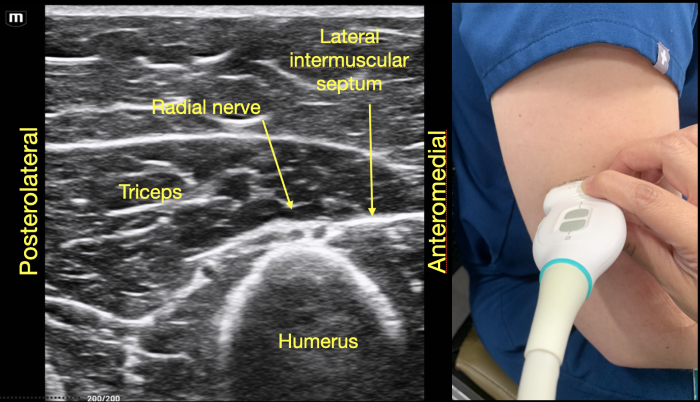

To identify the radial nerve in the mid-humerus position, have the patient in a seated position with the arm extended or held over the abdomen with the elbow flexed. Start with the probe placed transverse across the posterolateral mid-humerus and identify the radial nerve as a hyperechoic honeycombed structure lying directly on top of the humerus. At this point the radial nerve lies within the spiral groove and is also seen adjacent to the deep brachial artery. (Figure 7A)

As the probe is moved distally along the spiral groove, the posterior cutaneous nerve of the forearm can be seen branching from the radial nerve just prior to the lateral intermuscular septum (Figure 7D). In Video Clip 1, the radial nerve passes from the triceps into the biceps through the linear echogenic lateral intermuscular septum, which is a hyperechoic connective tissue layer separating the dorsal and anterior compartment of the arm.13

RadialNerve-Image1 Aug2024.pngFigure 1. Radial nerve lying directly on top of the mid-humerus adjacent to the deep brachial artery.

RadialNerve-Image6 Aug2024.pngFigure 6. Radial nerve joins the posterior cutaneous branch of the forearm proximal to the lateral intermuscular septum in the dorsal compartment of the arm.